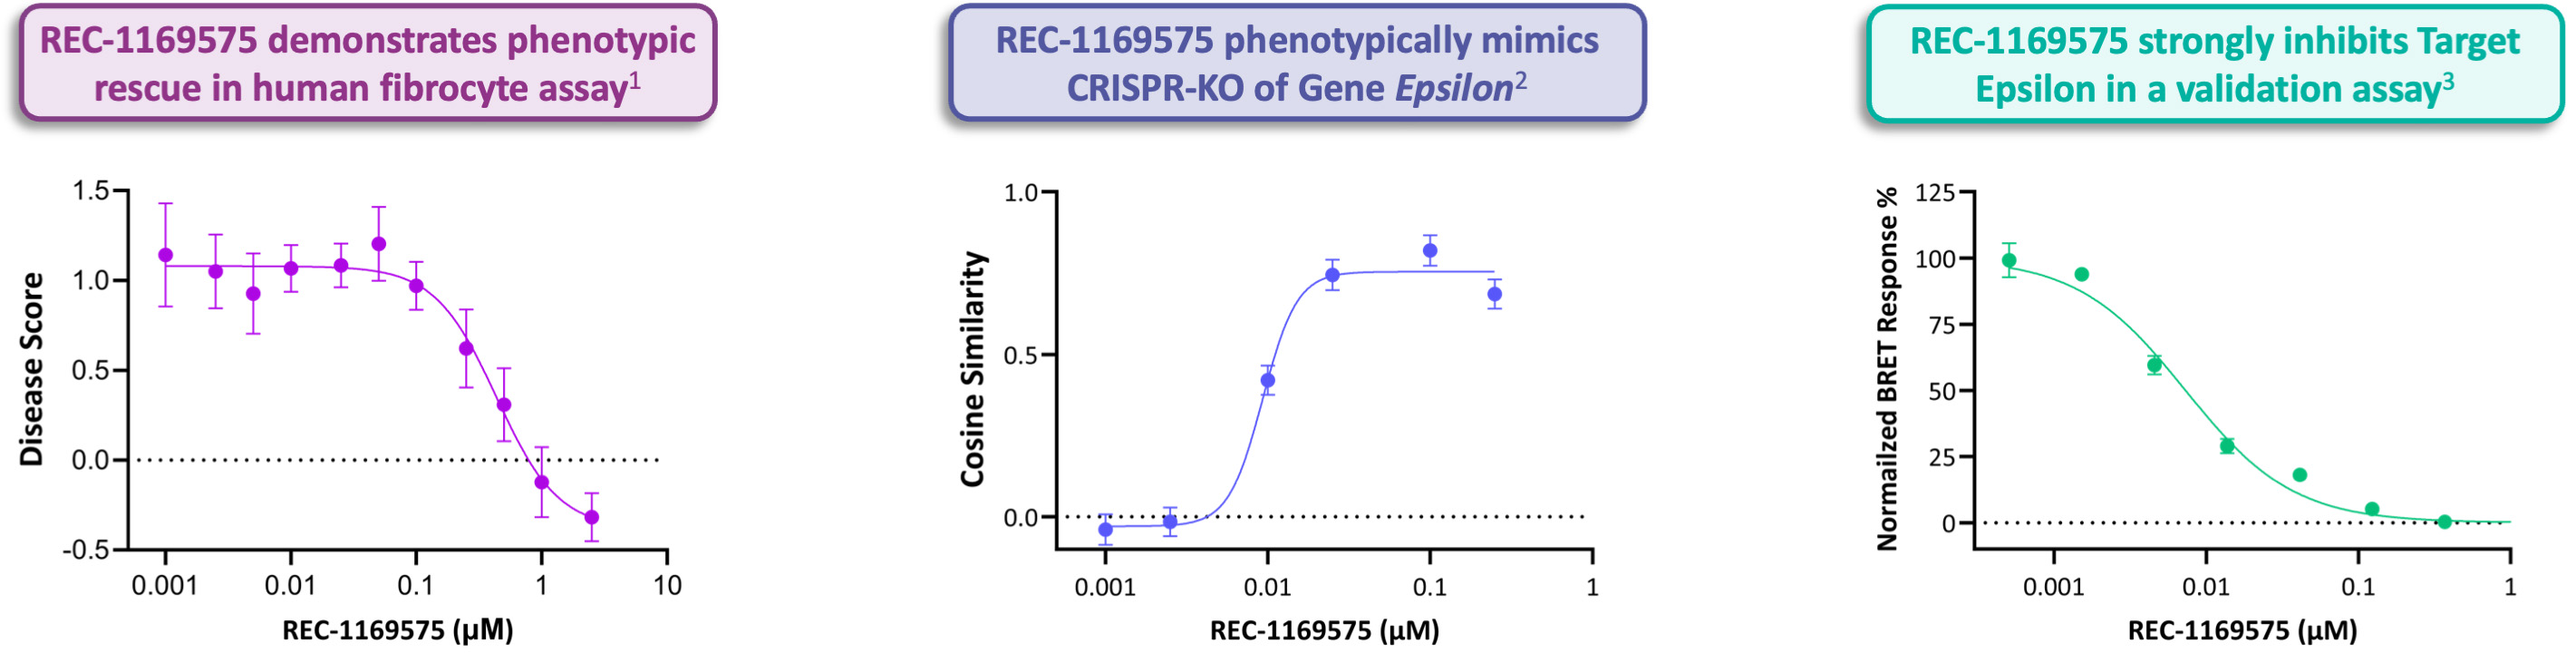

•In-licensed a program (Target Epsilon) that emerged from our fibrosis collaboration with Bayer that represents a novel approach to treating fibrotic diseases with compelling early data